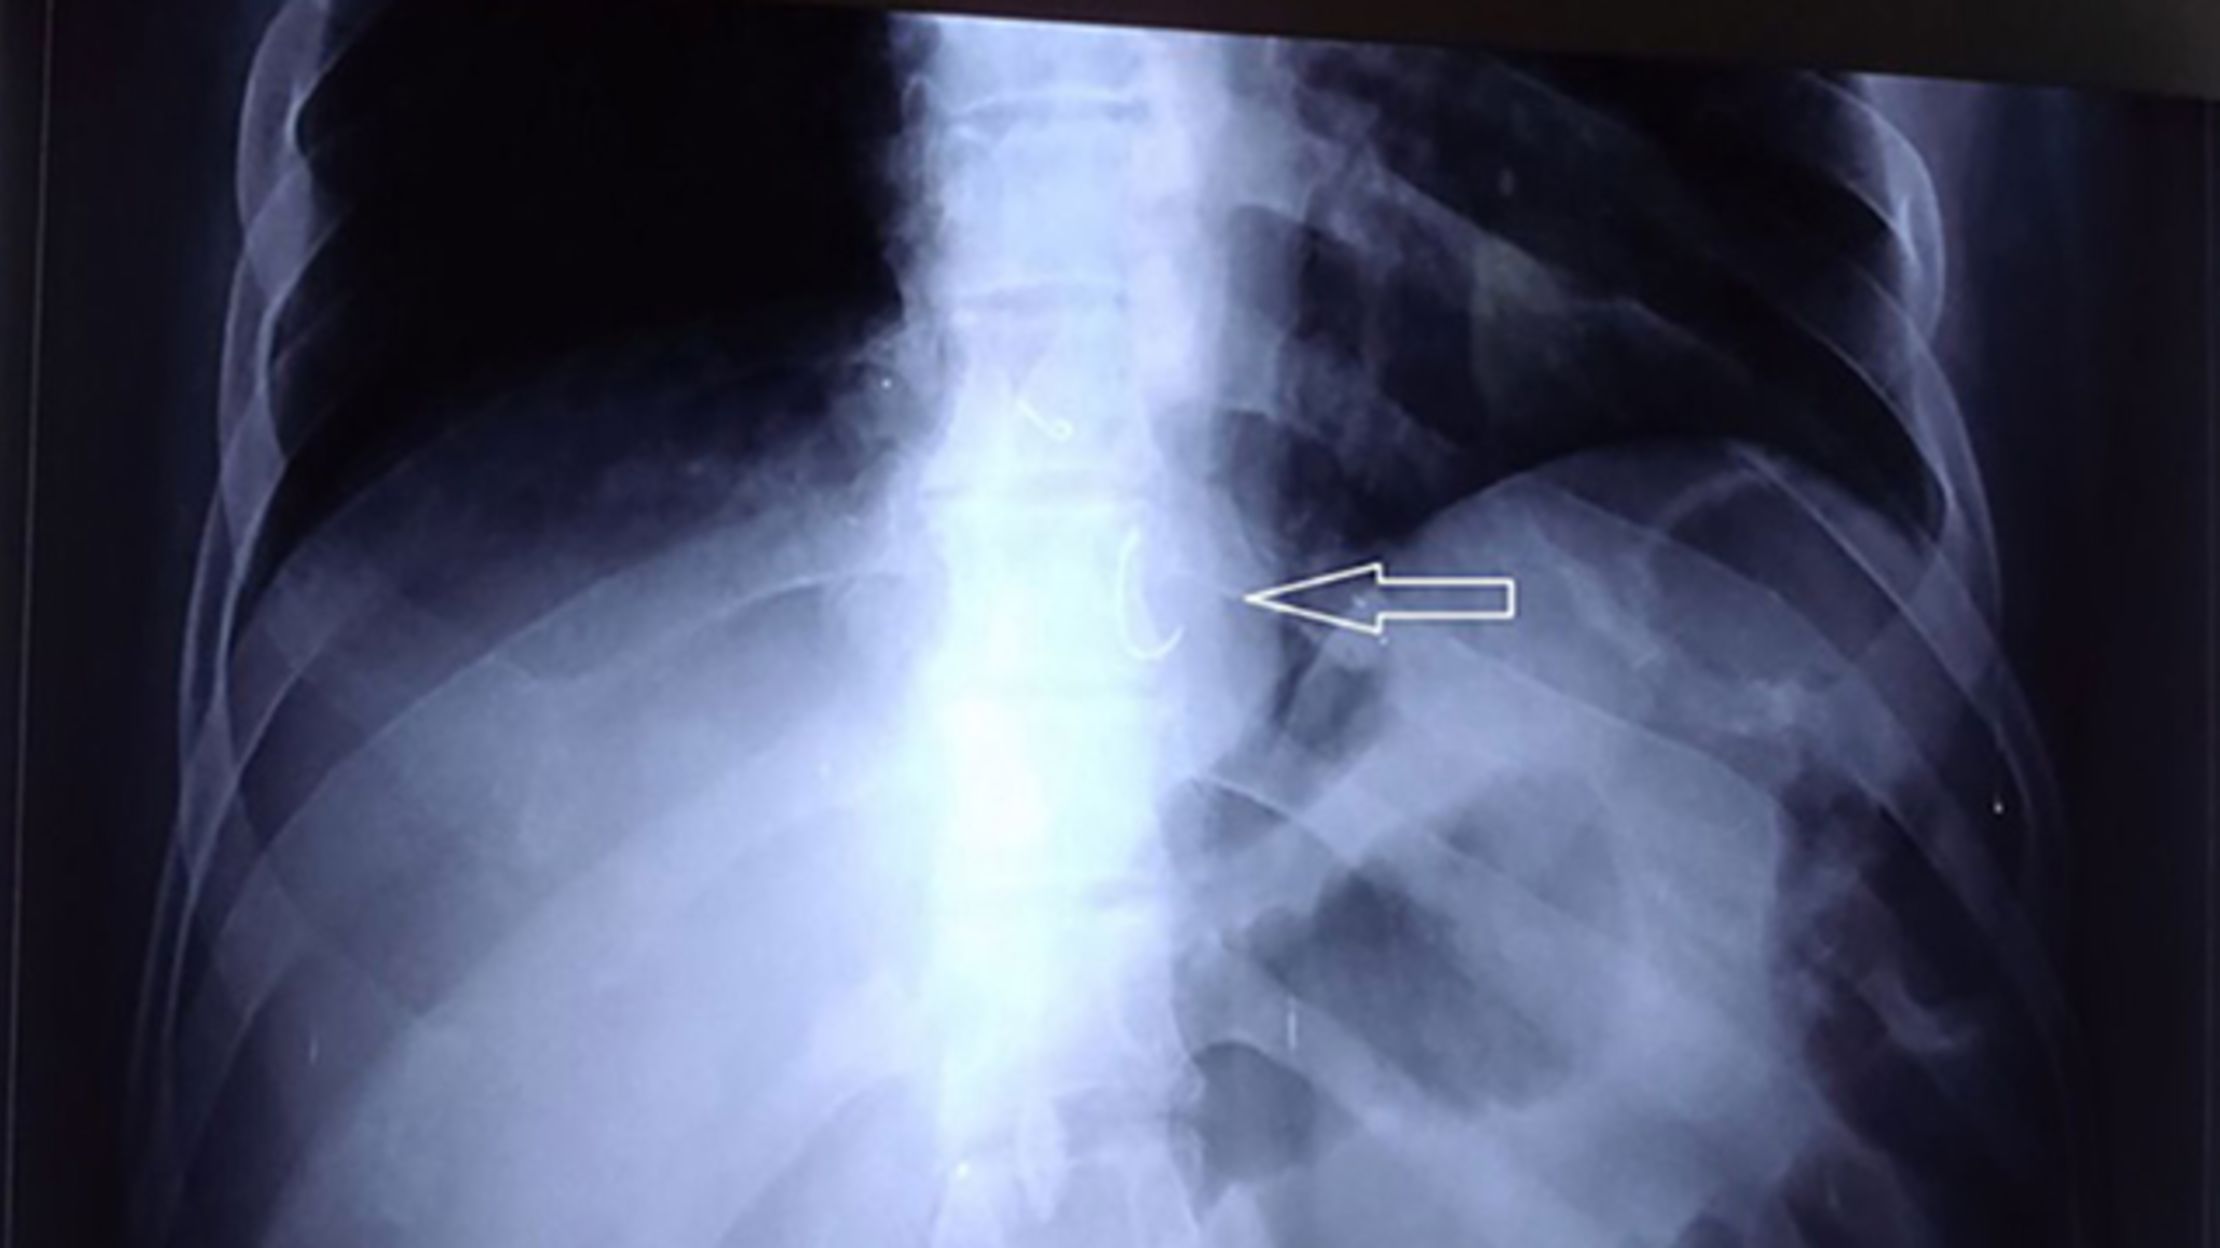

Man swallows dentures Man's dentures found lodged inside his throat 8